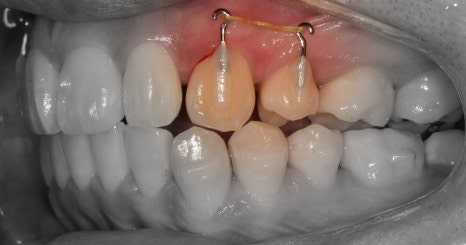

『발치 및 장치 부착, 인비절라인 진행』

표시를 해 둔, 갈고리처럼 생긴 것들은

Power arm 이라는 것들입니다.

이는, 치아들을 계획 했던 대로 정확히

이동을 시키게끔하는 보조수단으로 쓰입니다.

이후, 발치 공간이 조금씩 거의 다 폐쇄되면서

인비절라인 실버버튼을 부착시킵니다.

이것 또한, 보조도구입니다.

치열 전체를 덮는 인비절라인과 같이 맞물려서

정확한 치아의 위치 이동을 돕는 역할입니다.